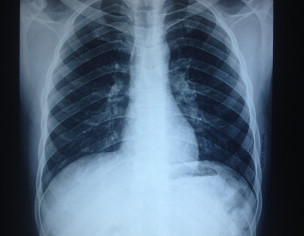

kindly examine the two chest x-rays from two different labs. my bro was hired job in UAE but in medical test he is declared unfit because of some kind of x-ray findings. These x-rays images are taken from two different labs from the 1st one where he was medically examined. Expert reviews required from radiologist and pulmonologist.

is B/l hilar prominence with old heald of the countries not accept these findings even if you dont have history of old or new infection/TB.

There is difference in exposure in both films. Any symptoms like fever, weight loss etc. Age of patient, smoking history?Dr Khawaja Yassir Rahman

2nd xray has some whitish shades in ur language like lymphednopathy

just because of this they reject

otherwise if pt is asymptomTic xray is normL

if he has cough short of breath he should go for Ace levels n ct scan